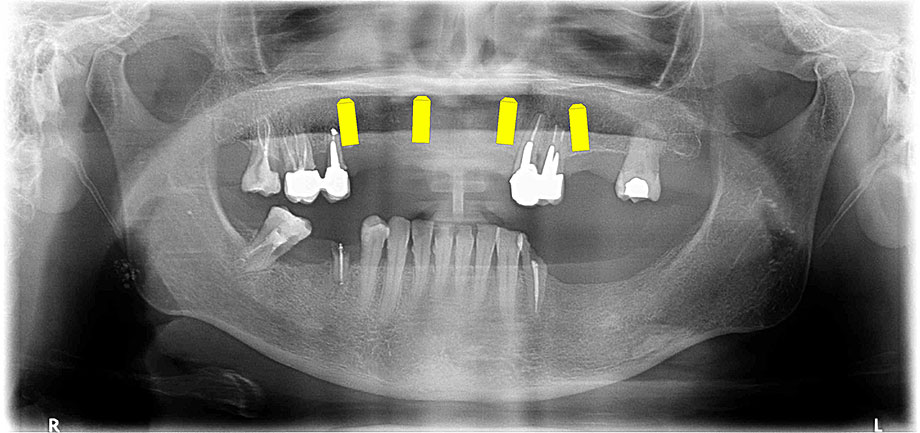

Implantologija